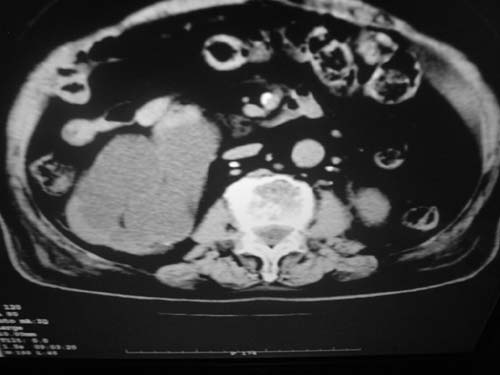

以下是引用余辉在2009-3-11 21:12:00的发言:[br]1肝脾多发钙化结节2右肾结石,右肾积水

以下是引用jiangjing在2009-3-12 17:05:00的发言:[br]1肝脾多发钙化结节2右肾结石,右肾积水 3胆囊炎[br] [br] 左肾囊肿